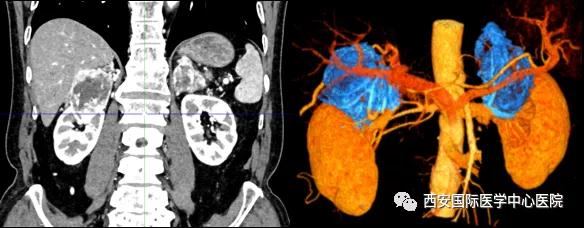

今年七十五歲的患者,來自陜西省商洛市,四月前因腰背部疼痛就診于當?shù)蒯t(yī)院,行CT檢查發(fā)現(xiàn)“右腎、雙側(cè)腎上腺占位,前縱膈淋巴結(jié)腫大,雙肺多發(fā)結(jié)節(jié)、胸椎骨質(zhì)破壞,考慮轉(zhuǎn)移瘤”。為進一步診斷治療,患者的兒子帶他來到西安某三甲醫(yī)院,查泌尿系CT提示“右腎占位性病變,多考慮腎癌,雙側(cè)腎上腺多發(fā)轉(zhuǎn)移灶,腹膜后多發(fā)腫大淋巴結(jié)”;行穿刺活檢提示“腎透明細胞癌”;并給予患者口服靶向藥物的治療方案。

自四月份至今,患者一直口服靶向藥物治療(阿昔替尼5mg 2次/日),期間無不良反應(yīng),目前腰背部疼痛癥狀也有所緩解,復(fù)查影像學(xué)資料提示瘤體較前縮小,腫瘤完整切除的可能性明顯提高;而且患者的兒子也是一名外科醫(yī)生,所以他更想為父親完成后續(xù)的手術(shù)治療。

患者一家慕名前來到西安國際醫(yī)學(xué)中心醫(yī)院找到楊增悅教授。楊增悅教授仔細看完患者的之前的影像學(xué)及病理資料后,診斷為:右腎透明細胞癌(T4N1M1);并安排他住院。而后,主管醫(yī)生及時為他完善了術(shù)前檢查及評估。7月15日,在麻醉手術(shù)中心柴偉主任、王彬榮副主任、李娟護士長、李瑞剛護士長及全體麻醉手術(shù)中心團隊的有力保障下,成功完成了這臺“大”手術(shù)。

手術(shù)由楊增悅教授主持,舒濤主治醫(yī)師、王東主治醫(yī)師主刀,黃怡醫(yī)師、王平醫(yī)師協(xié)助完成。由于第四代達芬奇機器人更加靈活和精準的特性,手術(shù)全程順利,尤其是完全精準的“解鎖”了右腎動脈和右腎靜脈的數(shù)十根交互纏繞的分支血管。術(shù)后患者麻醉恢復(fù)后生命體征平穩(wěn),順利返回泌尿外科普通病區(qū)進一步康復(fù)。